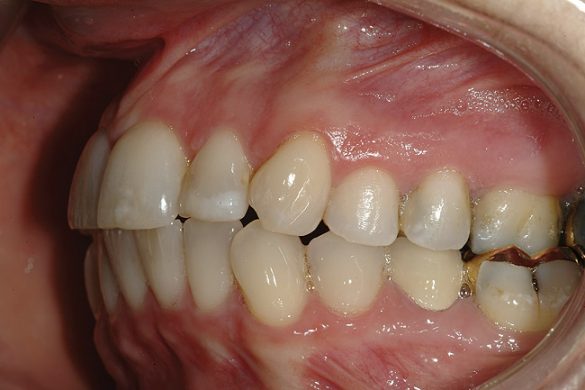

O pacientă în vârstă de 44 de ani s-a prezentat pentru evaluarea şi îmbunătăţirea zâmbetului ei. Acuza principală era reprezentată de afişarea neatractivă a coroanelor posterioare din aur, asociată cu petele albe inestetice de pe dinţii frontali (fig. 1, 2). Scopul ei convingător pentru solicitarea tratamentului a fost acela de a dobândi un „zâmbet deosebit”.

FUNCŢIONAL: La majoritatea dinţilor posteriori ai pacientei ce erau restauraţi cu coroane (fig. 6, 7) era importantă interpretarea minuţioasă a istoricului pacientei şi a rezultatelor evaluării ocluzale. Coroanele din aur de la nivelul 1.7. şi 1.4. prezentau orificii de uzură pe suprafeţele ocluzale, cu semne de minimă uzură pe celelalte coroane posterioare şi la dentiţia naturală. Era evidentă o uzură moderată pe coroana din aur a molarului 4.7.

Traumatismul ocluzal primar s-a observat la dinţii 1.5. şi 2.5. În intercuspidare maximă, s-a notat ocluzie deschisă la segmentele dentare frontale 1.3.-2.3. şi 3.3.-4.3. Dinţii 1.6. şi 4.6., precum şi 2.6. şi 3.6. erau în angrenaj invers (fig. 5, 8). Pacienta prezenta o ocluzie Angle Clasa I. Având în vedere rezultatele istoricului şi examinării s-a stabilit un diagnostic de disfuncţie ocluzală.

DENTO-FACIAL: Evaluarea zâmbetului pacientei a evidenţiat o dinamică labială maxilară medie şi afişarea ţesuturilor la zâmbire (fig. 2). Nivelurile gingivale maxilare inegale, exostoza osoasă vestibulară vizibilă corespunzător 1.6., dinţii rotaţi sau malpoziţionaţi, coloraţia de pe mai mulţi dinţi frontali, o „linie a surâsului inversată” , asimetria dentară şi un plan ocluzal maxilar neregulat reprezentau puncte semnificative în cadrul evaluării dentofaciale. Dorinţa pacientei de a avea un zâmbet ideal sau „generat de media” a accentuat dificultatea cazului. Dinamica labială maxilară medie şi afişarea în consecinţă a ţesuturilor a dictat evaluarea riscului pentru acest caz.